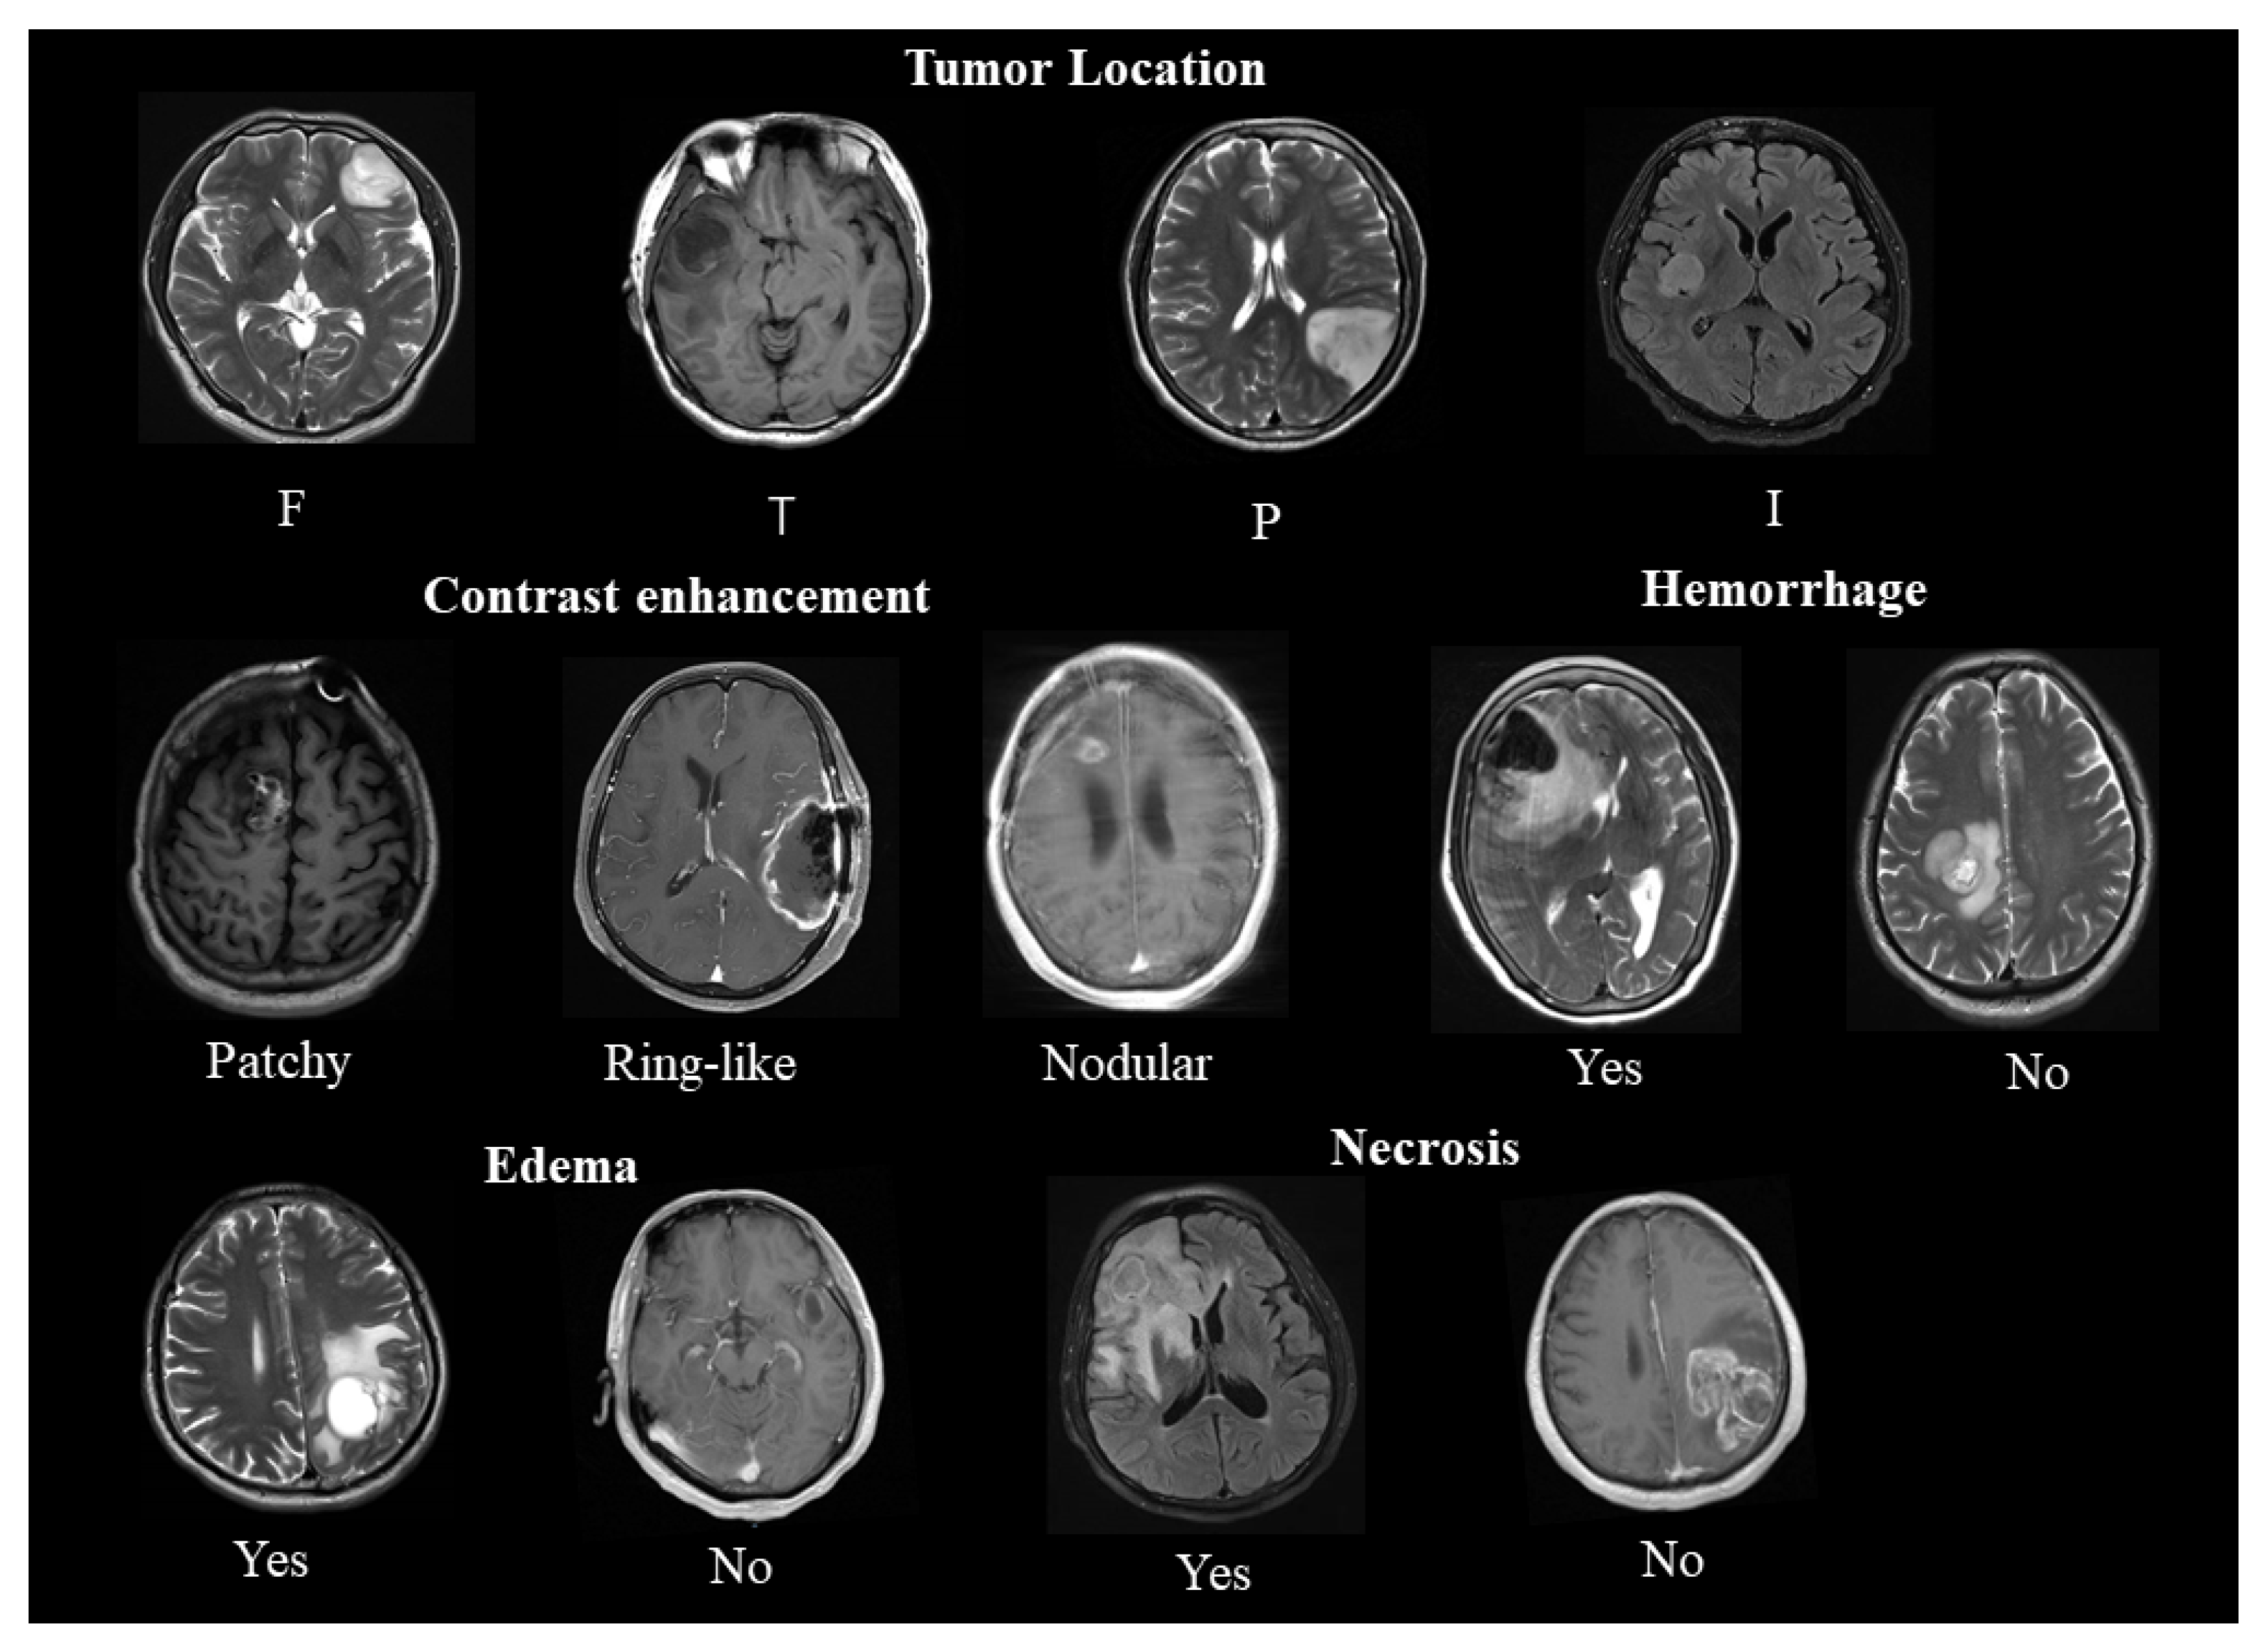

2.1. Location

2.2. Enhancement

2.3. Edema, Necrosis, and Hemorrhage